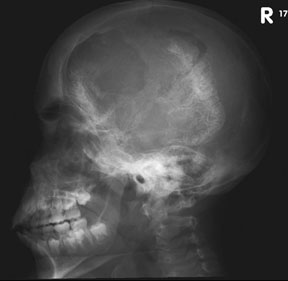

Sturge (1879) reported the case of a child with facial “port-wine stain,” epilepsy, buphthalmos, and a dark choroid.204 Schirmer had noted the association of the facial vascular malformation and glaucoma in 1860.3 Weber (1922) reported brain X-ray findings of parallel streaks (“railtrack” sign), which he interpreted to represent calcific changes (Fig. 19).205

Fig. 19. Sturge-Weber syndrome. Lateral skull X-ray of an adult with Sturge-Weber syndrome with the typical tram track calcification of the pial angioma.